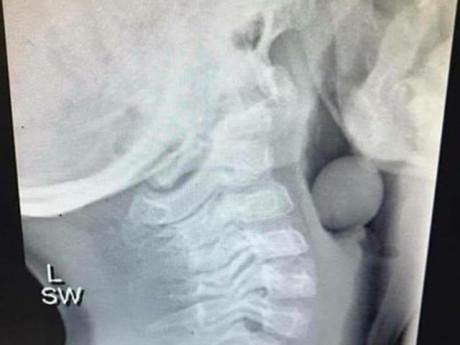

Bức ảnh cho thấy cổ họng của bé trai đã bị một vật gì đó chặn lại và mắc kẹt bên trong. Angela viết: “Bạn có biết cái gì trong bức ảnh chụp x quang này không? Đó là một quả nho. Một quả nho đã chặn ngay họng của một đứa trẻ 5 tuổi. Cậu bé đã được phẫu thuật để loại bỏ vật cản ra. May mắn khi một phần đường thở của cậu bé không bị chặn nên đã không có kết cục tồi tệ nào xảy ra.”

Hình ảnh phim chụp X-quang cổ họng của bé trai bị một quả nho chặn.